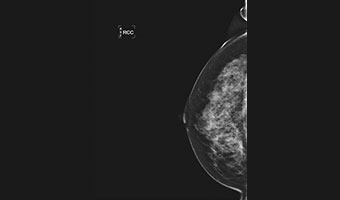

低剂量高清图像

微小病灶,清晰呈现

放大摄影功能,微小病灶无处遁形

低剂量高清晰兼顾

进口钼靶球管 X射线更适合乳腺检查 管球寿命更高 钼铑双滤过,根据乳房致密度自动智选

先进的乳腺成像算法